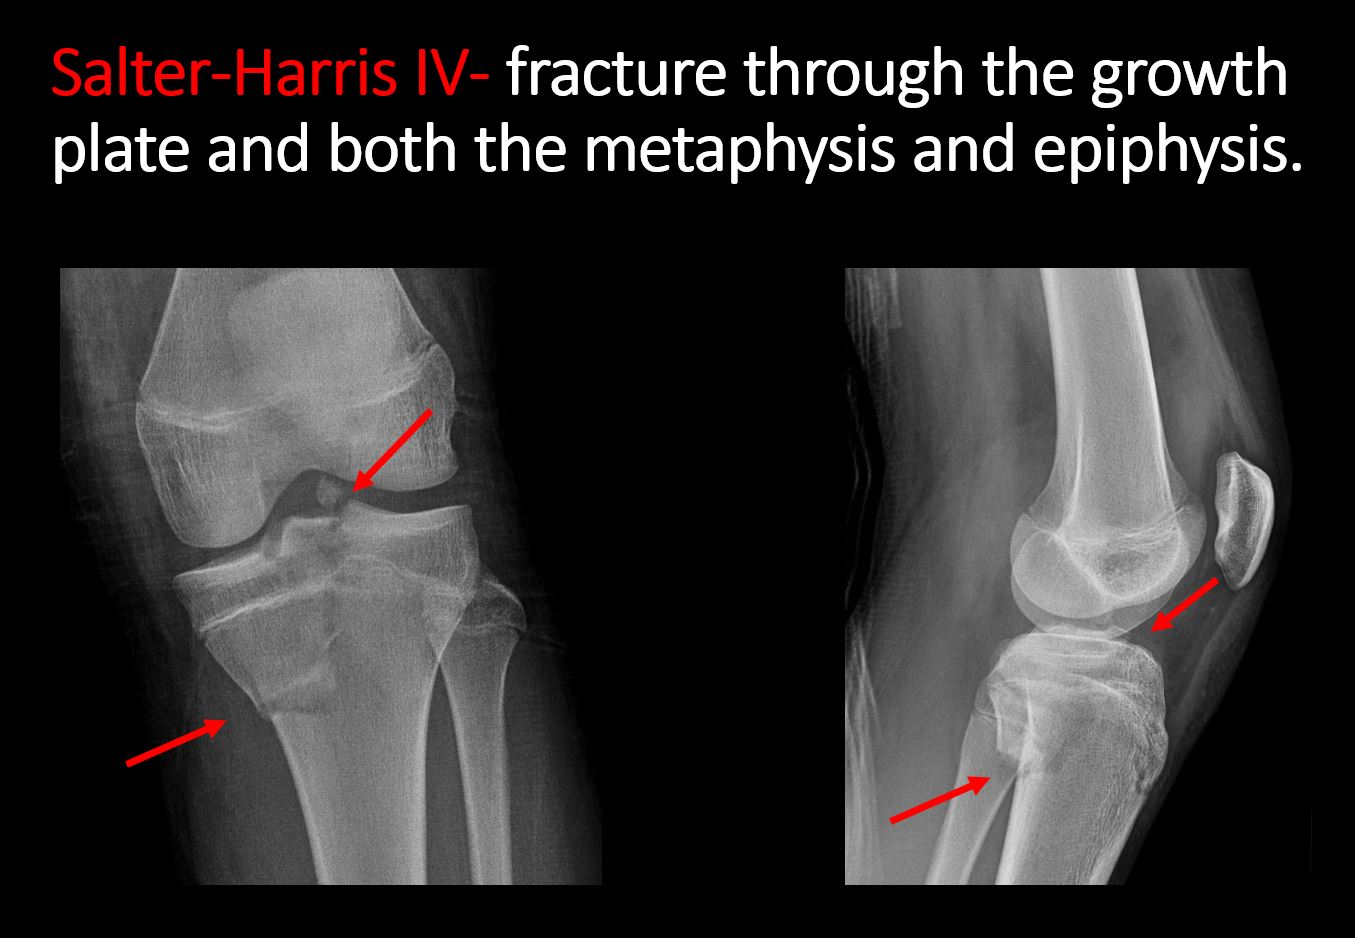

There is a fracture through the metaphysis, physis, and epiphysis which extends into the joint space with or without angulation or displacement (S-H IV). |

N/A | NA |